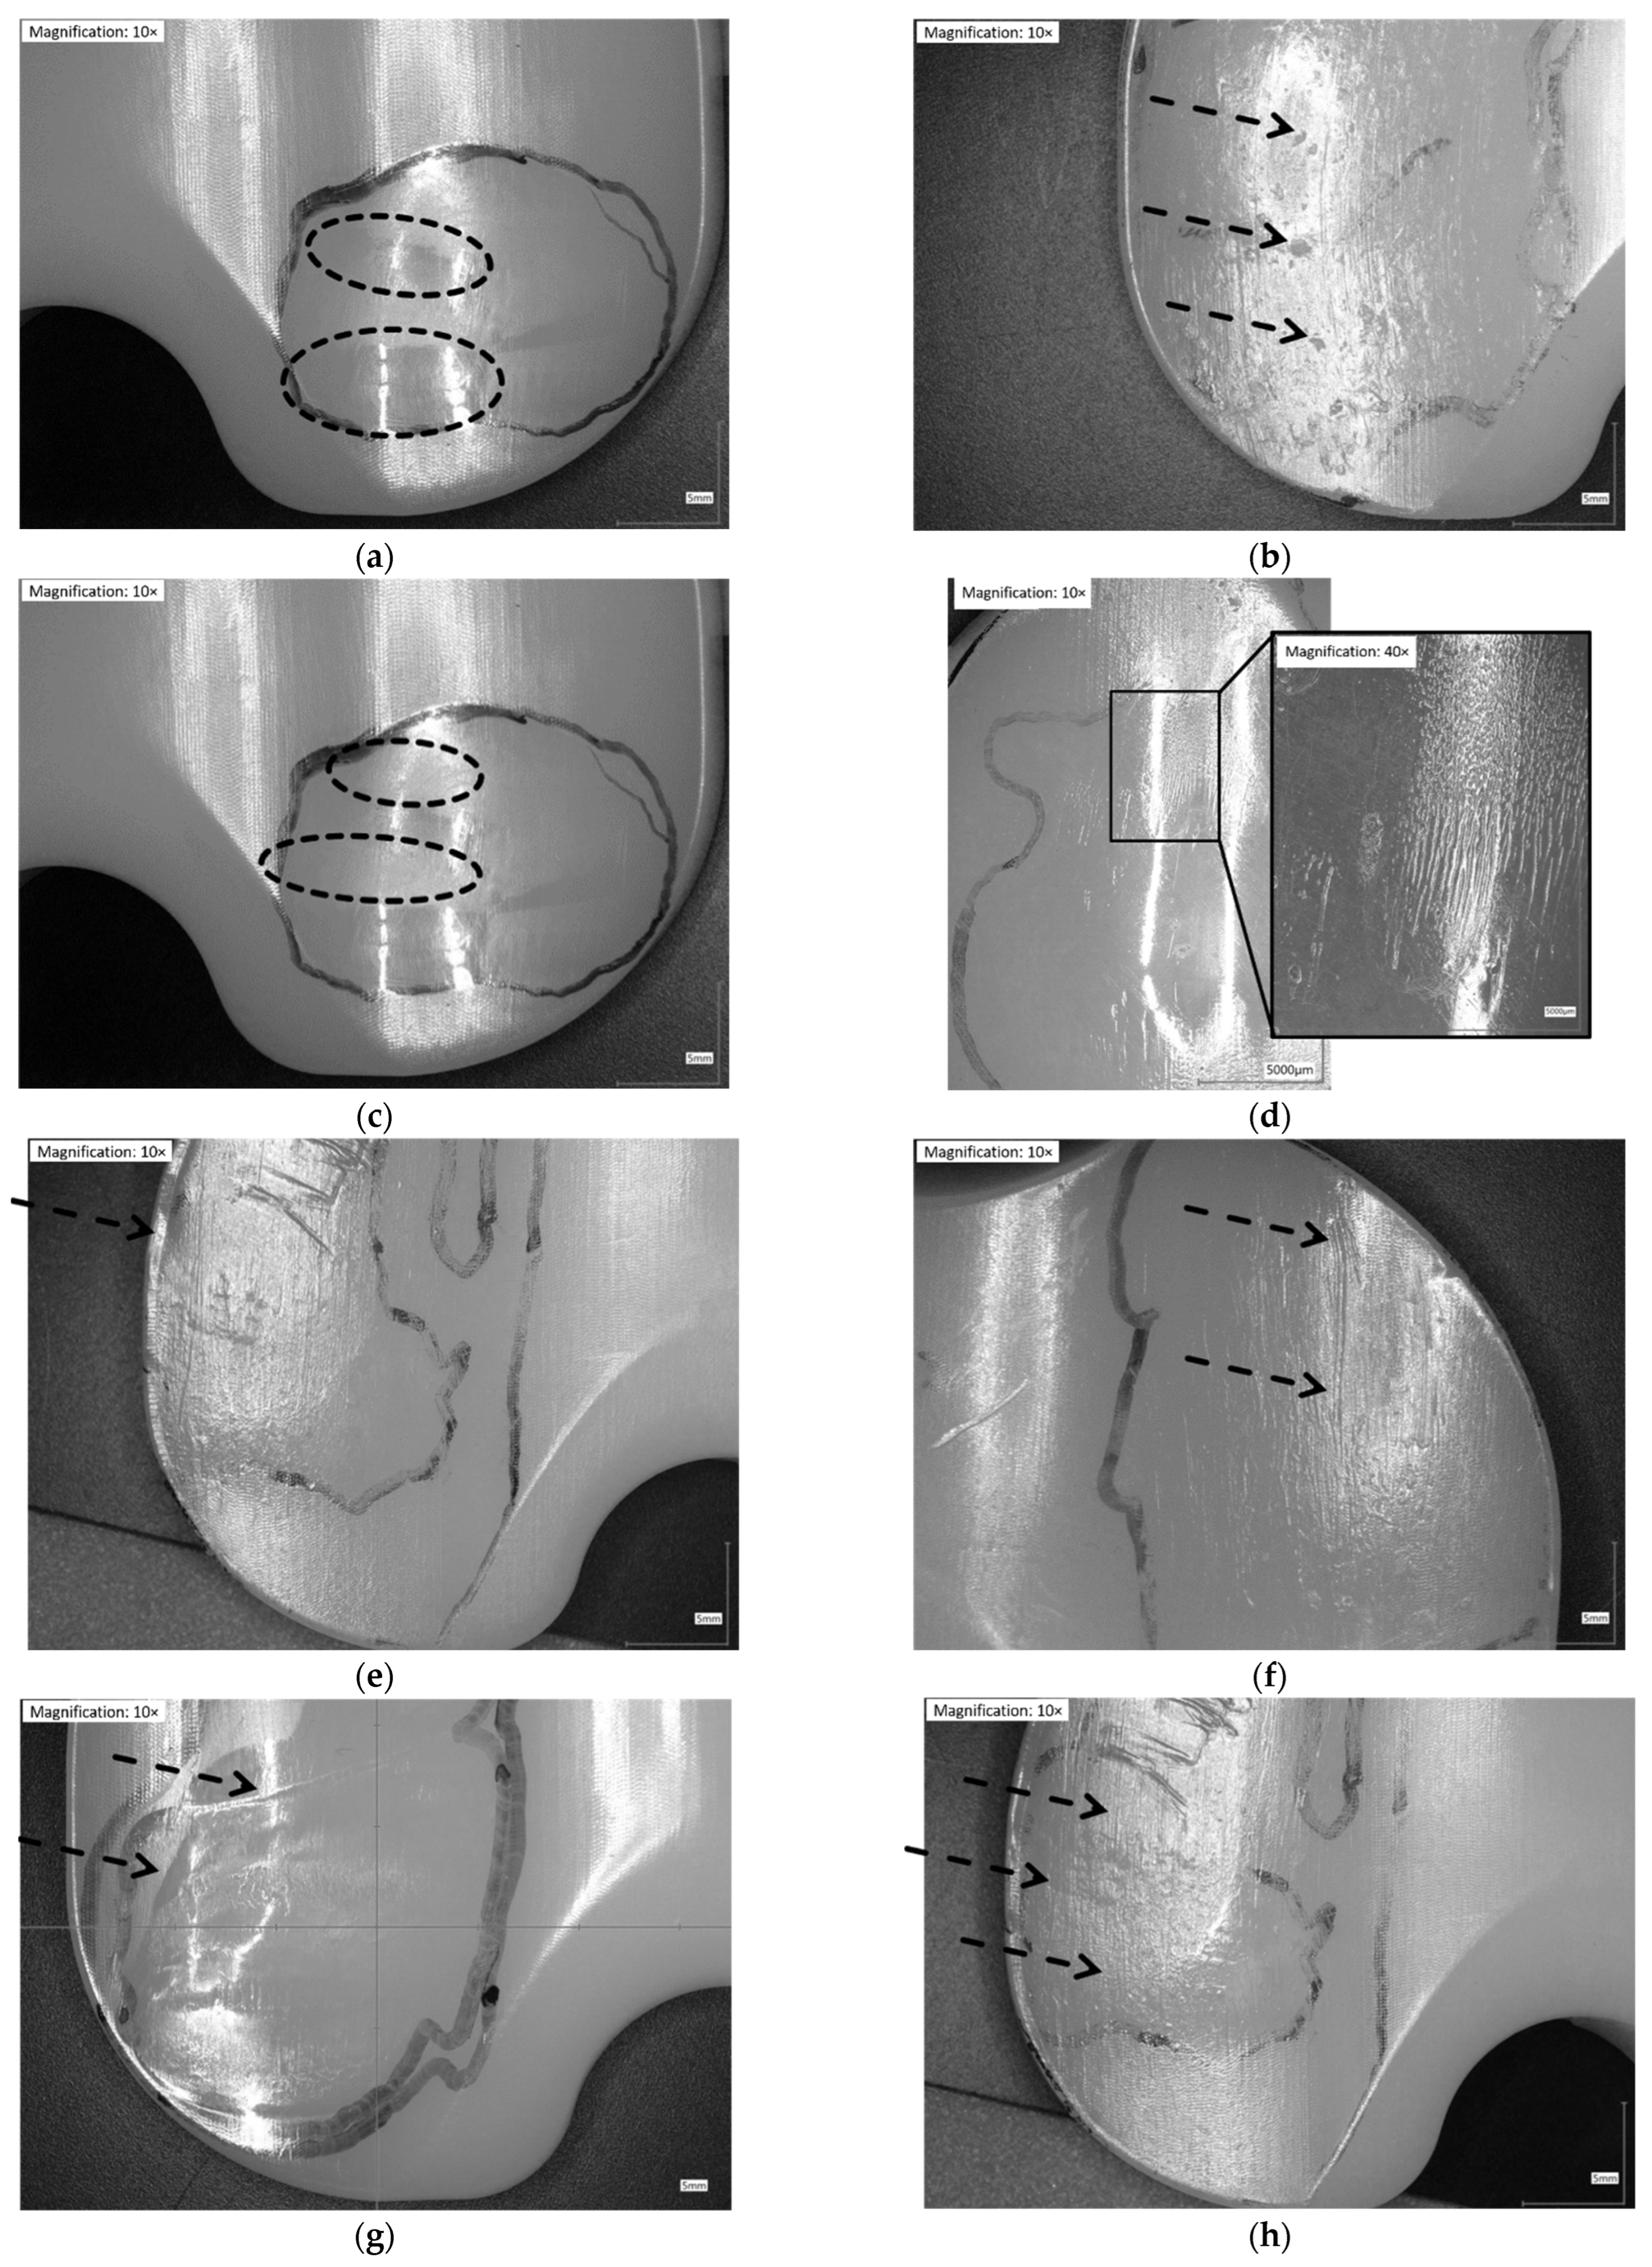

Following Wasilewski et al. [25], the proximal surface of the inserts was dissected in ten areas (Figure 1). The articulating surface was examined microscopically with magnifications of 10×. Based on similar observations in literature [7,24,25,26,29,32,33,34], the following patterns of wear were identified and related to each of the ten areas in Figure 2.

Figure 2.

Illustration of wear patterns found on the retrieved UHMW-PE inserts. (a) Burnishing: polishing of the surface → surface appears smoother than manufacturing marks; (b) Pitting: depressions in articulating surface with irregular shape (2–3 mm across and 1–2 mm deep); (c) Abrasion: roughening of the surface, which results in a shredded or tufted appearance → surface appears rougher than manufacturing marks; (d) Striated wear pattern: described in a study [9] as regularly spaced striations in an anterior-posterior direction; (e) Rim-runner [24]: propagation of the worn areas on the elevated, rounded rim of the insert, with a localized form of creeping; (f) Third-body wear: parallel scratches causing thick scars of material removal (sometimes distinct holes from temporarily embedded debris at one end); (g) Deformation/Deep wear: distinct material accumulation on or around articulating areas; (h) Scratching: indented lines, generally in antero-posterior direction with only slight material removal.

Except for delamination and embedded debris, which were not found on any inserts, each of the remaining eight wear patterns was found on the retrievals. Some wear patterns did not occur on the simulator-tested inserts (Figure 8). No rim-runner, no deformation, no pitting, and only slight third-body wear were found on the inserts in the CoCr-ISO simulation. On the TiN-IR and TiN-TS inserts, six of the eight wear patterns were found. On the CoCr-TBW inserts, seven of the eight wear patterns were found.

Figure 8.

Distribution of each wear pattern on the damage score for retrieved and simulator-tested inserts. Significances, marked with asterisks (one asterisk *: p < 0.05 and two asterisks **: p < 0.01), are shown to facilitate the comparison of retrievals with the simulator-tested groups. (Maximum score for each wear pattern was 8, Maximum total damage score was 64).